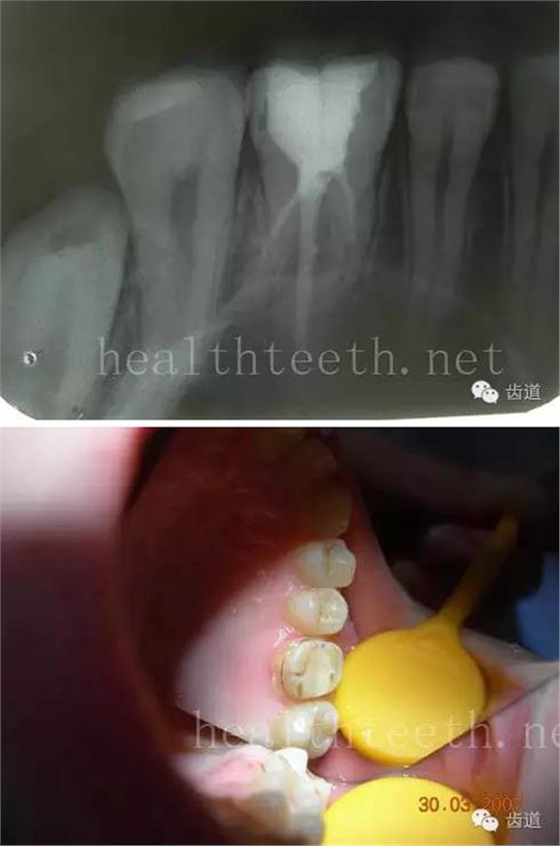

因?yàn)楸旧聿桓阏衬げ。占降牟±邢?,大多是同事收?/span> 頰粘膜扁平苔蘚 舌粘膜扁平苔蘚 舌緣創(chuàng)傷性潰瘍 長期戴活動義齒不當(dāng)或是戴不良修復(fù)義齒造成的口腔粘膜潰瘍,應(yīng)該引起高度警惕,因?yàn)檫@種潰瘍?nèi)菀装┳?/span> 黑毛舌 舌息肉,該患者同時伴有胃、食管息肉,后來看內(nèi)科了,具體情況不詳 四、孩子的牙齒問題 乳牙未退,牙根穿出牙齦對上唇粘膜造成刺激 乳牙滯留,也是孩子在退牙過程中最容易遇到的問題 五、牙齒發(fā)育上的問題 變色牙 氟斑牙 釉質(zhì)發(fā)育不全 四環(huán)素牙 牙神經(jīng)治療后的牙齒變色 10歲孩子剛剛萌出的牙齒變色 2、埋伏牙 左上乳3滯留,恒3未見萌出,曲面斷層片顯示牙齒埋伏 通過CT片確定埋伏牙齒具體的位置,顯示距離左側(cè)上頜竇很近,偏唇側(cè),這為手術(shù)定位提供了方便 手術(shù)中切斷、完整拔出,未損傷上頜竇 其他埋伏牙 3、多生牙 病例1 病例2 病例3,同時多生兩顆牙齒 4、各種畸形牙 畸形過小牙 融合牙:恒牙和乳牙都可以發(fā)生融合的情況(兩顆牙齒長在了一起) 畸形中央尖:在牙齒的中央,兩個牙尖之間又多長出一個牙尖,由于進(jìn)食的磨耗很容易造成磨穿,神經(jīng)就會與外界相通,出現(xiàn)牙髓炎的癥狀 六、牙齒的外傷 牙冠折斷 牙根折斷 烤瓷牙打樁修復(fù)后牙根折斷 外傷后牙齒的全脫位,應(yīng)該保留牙齒盡早做再植手術(shù) 七、牙齒的慢性損傷 牙頸部楔狀缺損 牙冠劈裂及完整拔除后的情況 牙根縱裂及拔除后的情況 牙隱裂,牙齒表面有肉眼看不到的裂紋,細(xì)菌通過其進(jìn)入牙髓,容易出現(xiàn)牙髓炎癥狀,嚴(yán)重可以造成牙齒的劈裂 這是一位來中國學(xué)習(xí)的俄羅斯大學(xué)生的牙齒,已經(jīng)做過了根管治療,牙齒咬合面有隱裂,通過鋼絲結(jié)扎固定,做鑄造金屬冠修復(fù)。 八、牙髓炎、根尖周炎 下面圖片都是慢性根尖周炎的病例,有了齲齒,進(jìn)一步發(fā)展就是牙髓炎,如果此時沒有得到及時的治療,疾病會逐漸發(fā)展破壞到根尖的骨質(zhì),將骨質(zhì)破壞后就在牙齦上出現(xiàn)一個膿瘺,此時患者不再感覺到牙齒的疼痛了,往往忽視了治療,但是這種不痛并不是疾病好轉(zhuǎn)了,而是因?yàn)榧膊〉难仔詽B出得到了引流,這個膿瘺會出現(xiàn)有時候變大了,有時候又變小了,但是如果不治療是不會自己愈合的,只有經(jīng)過完善的根管治療后才有好轉(zhuǎn)的可能,但是在疾病的治療中時間是起決定作用的,時間拖得越晚,好轉(zhuǎn)的可能性越小,經(jīng)過根管治療后如果膿瘺還是沒有消失,就需要做根尖刮治術(shù),如果仍然沒有好轉(zhuǎn),就只能做根尖切除術(shù)了,這對牙齒的穩(wěn)固是不利的。下面圖片中在膿瘺中插入了一個牙膠尖,是我們做根管充填用的材料,是非常軟的,就是在口腔牙齦瘺管的地方插進(jìn)去,通過拍牙片可以清晰地看到它到達(dá)的位置,從而確定發(fā)病的牙齒,此處是為了讓大家看得更清楚。 門牙兩個膿瘺 烤瓷牙修復(fù)后牙齦出現(xiàn)兩個膿瘺,插入牙膠尖,牙片顯示牙膠尖到達(dá)的位置就是根尖炎癥的位置,根尖骨質(zhì)密度降低(發(fā)黑的地方) 牙齒根尖膿瘺,治療前、中、后的圖片對照,完善根管治療后膿瘺明顯消失了 牙髓炎和根尖炎治療的關(guān)鍵就是根管治療 合格的根管充填治療 不良的根管充填治療 九、關(guān)于智齒(第八顆牙) 四顆長不出來的智齒 智齒反復(fù)發(fā)炎造成的頰瘺,膿腫切開引流后面部會留疤 智齒造成的頜骨囊腫,手術(shù)切除后需要植骨 十、各種錯合畸形 開合 深覆合 深覆蓋,上頜前突 反合(地包天) 牙齒排列擁擠 來源:牙醫(yī)愛看的 KQ88口腔醫(yī)學(xué)網(wǎng)